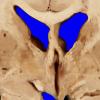

Subcortical Arteriosclerotic Encephalopathy (5)